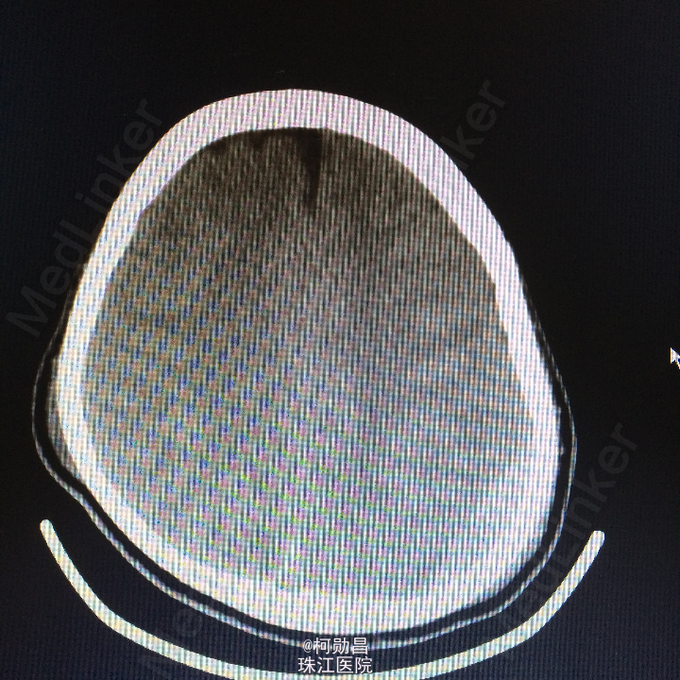

主诉:颅骨损伤后头痛、头晕2天 病史:患者于2天前骑摩托车时与机动车相撞,跌伤头部,至口角、眉弓处多处裂伤出血,左侧外耳道流血,当时患者无意识不清、肢体抽搐等。随即呼叫120送至医院。行头颅CT查示:左顶部硬膜下血肿,蛛网膜下腔出血,予相应治疗后病情稳定 。

查体:脑膜刺激征阳性 辅助检查:复查头颅CT及三维颅骨重建提示:血肿较前吸收,颅骨多发骨折,左额部较为明显

诊断:重型颅脑损伤,脑脊液耳漏、颅骨多发骨折